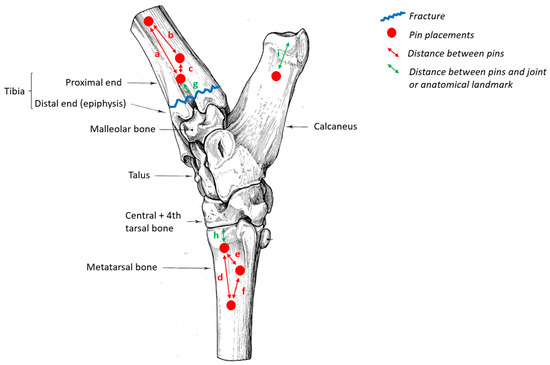

| Distances between the Pins | Values (cm) |

|---|---|

| a | 5 |

| b | 3 |

| c | 2 |

| d | 4 |

| e | 2 |

| f | 3 |

| g | 2 |

| h | 1.5 |

| i | 3 |